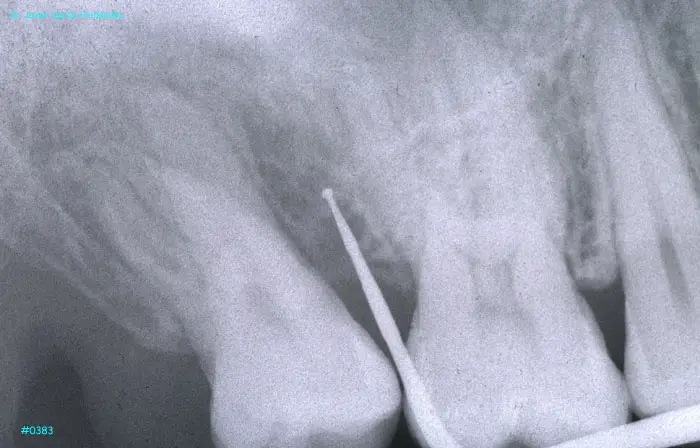

imagen 435